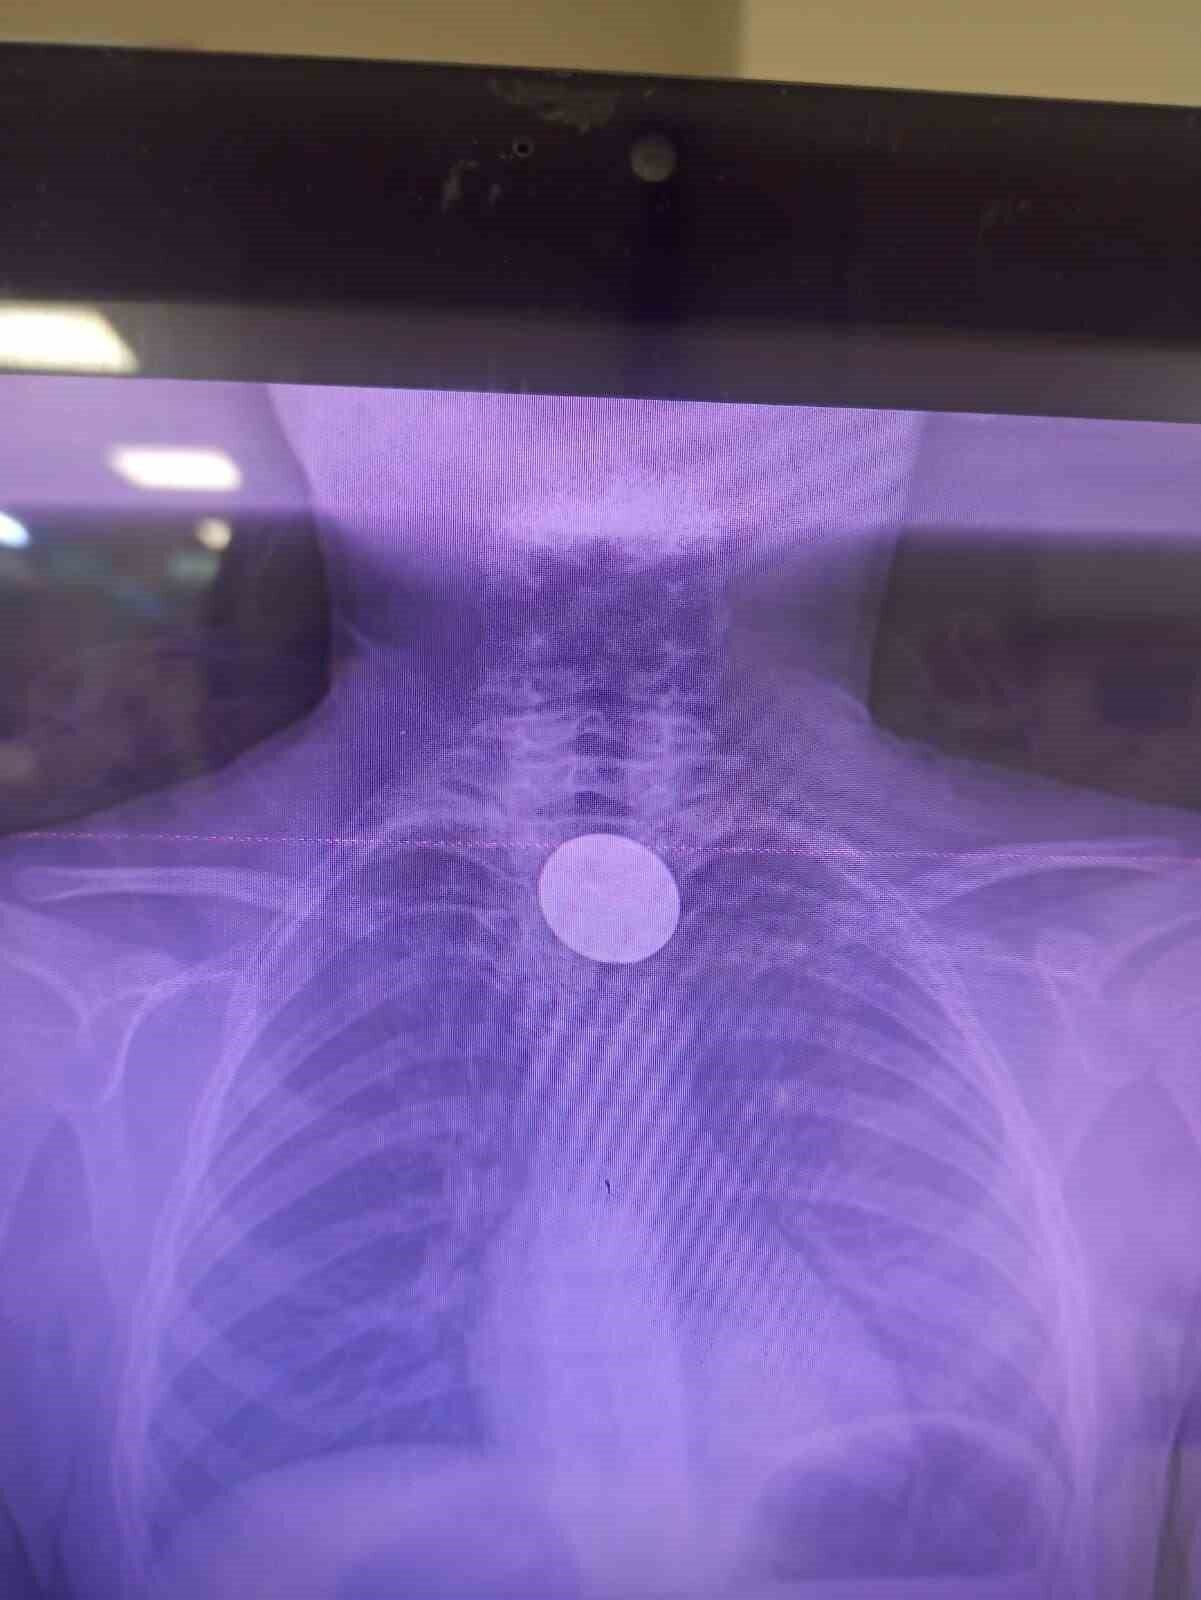

Yabancı cisim yutma şikayetiyle ailesi tarafından Siirt Eğitim ve Araştırma Hastanesi’ne getirilen 8 yaşındaki Y.K., yapılan ilk değerlendirme ve görüntüleme tetkiklerinin ardından ilgili branşlarca operasyona alındı. Y.K.’nın yemek borusuna kadar ilerlediği belirlenen madeni para, gastroenteroloji uzmanı Dr. Yaren Dirik ve kulak burun boğaz hekimi Yasin Gökçınar tarafından müdahale edilerek çıkartıldı. Operasyonun ardından bir süre gözlem altında tutulan Y.K., tedavisinin tamamlanmasıyla taburcu edildi.

Siirt Eğitim ve Araştırma Hastanesi Başhekim Yardımcısı Uzman Dr. Burak Özkan, çocuk hastalarda yabancı cisim yutma vakalarının ciddi riskler oluşturabileceğini ifade etti. Uzm. Dr. Özkan, “Hastanemize başvuran 8 yaşındaki hastamızın yemek borusuna kaçan madeni para, gastroenteroloji ve KBB ekiplerimizin koordineli ve titiz çalışmasıyla herhangi bir komplikasyona yol açmadan başarılı bir şekilde çıkarılmıştır. Operasyon süreci sorunsuz geçmiş olup hastamızın genel durumu iyidir” şeklinde konuştu.